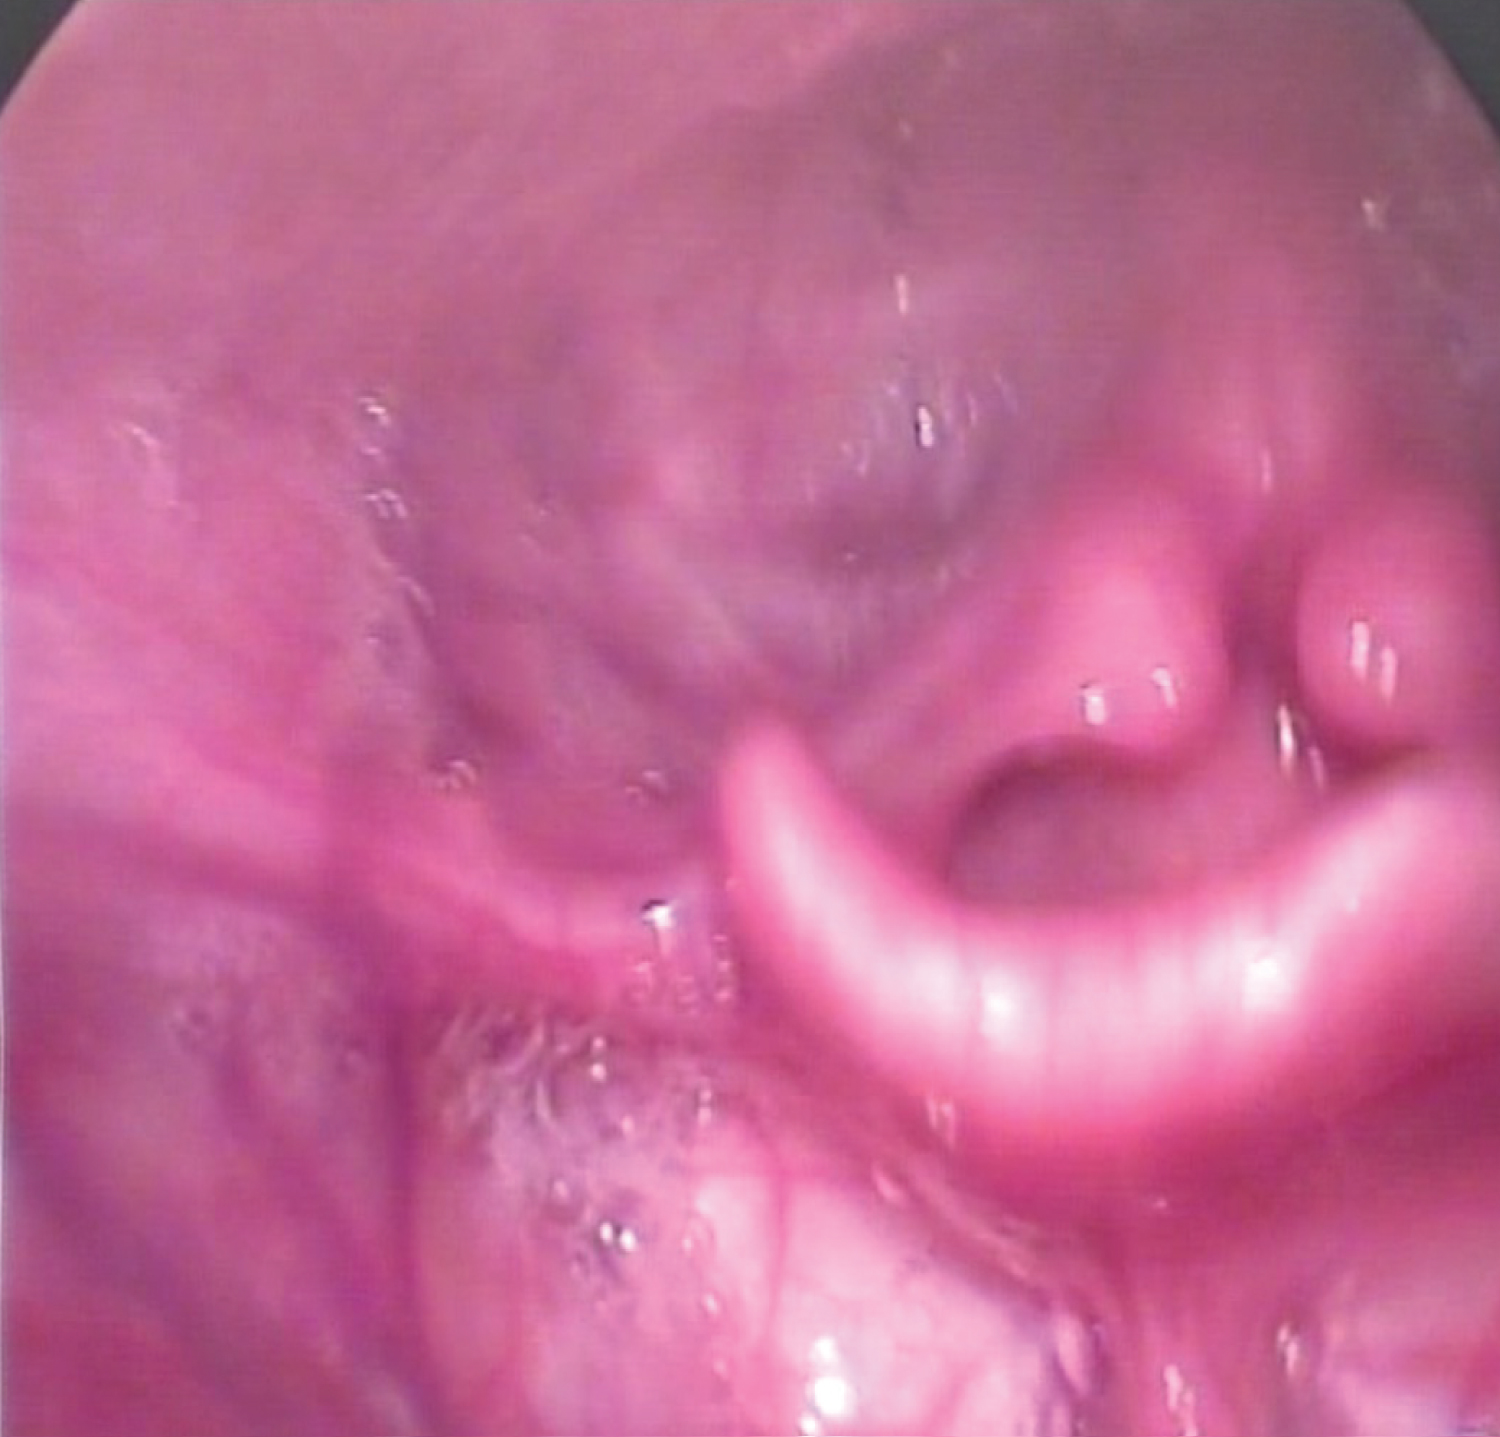

The case was an 11-year-old girl with the Fraser syndrome. Her fingers and toes were joined, which was developed in childhood through the surgery for interfingers folds. Both eyelids were also fused to the face due to the failure to separate the connective tissue during the fetal period. Due to the need for extensive surgical procedures on her eyes, the child was referred to speech therapy for airway examination and status to be evaluated for laryngoscopy of the larynx. Visual evaluation of the larynx was performed using video laryngoscopy, and the acoustic characteristics of voice samples, including vowel sustaining and connected speech, were assessed using Praat software. Auditory-perceptual evaluation of connected speech samples was performed using the GRBAS scale. On this scale, grade of hoarseness, roughness, breathiness, asthenia and strain were assessed on a 4-point Likert scale. On this scale, the severity of the disorder is expressed in each case with a point ranging from 0 to 3, indicating 0 as normal voice and no disturbance and 3 as severe defects in the voice. Auditory-perceptual evaluation was performed by a speech-language pathologist with over 10 years of experience in the evaluation and treatment of voice disorders. Due to the specific circumstances and blindness of the child, the laryngoscopic procedure was performed after several attempts because of poor co-operation. Laryngoscopic findings showed a glottic web extended from anterior to posterior, albeit a cleft was observed in the posterior laryngeal inlet through which the child breathed (Figure 1 and Figure 2).

Figure 2: A photo of the patient's larynx by video laryngoscopy during breathing. View Figure 2

Fraser syndrome is one of the rare congenital syndromes characterized by failing the separation of membrane webs, between the parts of the body that must undergo resorption during embryonic development [4]. Since the larynx is one of the parts with membrane fusion, this syndrome may also affect the larynx and especially the vocal folds. This laryngeal disorder can cause for respiration and vocalization. The congenital glottic web is actually a condition in people with this syndrome that causes respiratory and vocalization problems [9,10]. As previously stated, the case reported in this study also had severe problems with vocalization and due to its vocal folds involvement. According to the results of acoustic studies of the voice, her speech had no vocalization in most cases and was similar to whispering. Therefore, this person probably overcomes this problem by using subglottic pressure and noise development in most cases, and has maintained her ability to communicate through speech (Figure 3). However, the voice created in this way has developed a connection with unpleasant and monotonous voice quality. Based on acoustic evaluations, the fundamental frequency of a child's voice sample is greater than the normal range of the fundamental frequency of girls in both vowel sustaining and connected speech [13]. The jitter and shimmer values of the child's voice, which were 1.52 and 15.34, respectively, were much higher than the normal range, indicating a high degree of voice disturbance. The normal range for jitter is less than 0.5 and for shimmer is less than 3 [12,14]. The harmonics-to-noise ratio (HNR), given that its normal value in girls should be above 13, was below this value in both vowel sustaining and connected speech tasks, indicating the absence of normal voice in the individual [15]. The results of auditory-perceptual voice assessment using the GRBAS scale also confirmed the results of acoustic assessments and indicated significant problems with individual voice quality. As shown in Figure 1 and Figure 2, the person was breathing through a cleft in the posterior larynx. Given that other reports of the disease did not specify the acoustic and auditory-perceptual characteristics of the voice for these patients [9,10], the data in this report may be helpful in this regard, and future reports in these patients should be reviewed frequently for the acoustic and auditory-perceptual characteristics of their voice (Figure 3).